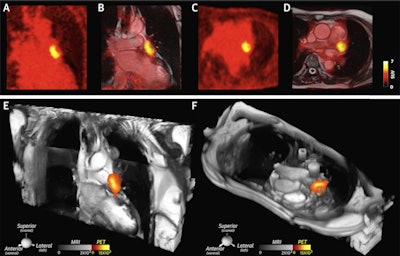

A large thrombus is seen in the left atrial appendage (LAA) behind the device on (A and B) the coronal PET and PET/cardiac MRI images as well as (C and D) the axial PET and PET/cardiac MRI images. (E and F) 2D balanced steady state free precession cines stacks in the coronal and axial planes have been combined into a single 3D dataset and fused with the 3D PET data. In these multimodality images, the PET and MR data are both displayed in 3D, creating a volumetric depiction of the heart and the thrombus/Cu-64 FBP8 containing LAA. Volume-rendered images in the oblique coronal and axial planes confirm the presence of thrombus in the LAA. (A to F) The thrombus produced by the closure device is contained within the LAA, and no evidence of thrombus is seen elsewhere in the heart or thorax. Image courtesy of JACC: Cardiovascular Imaging.SUVmax values in the LAA were significantly higher in patients with clots in the LAA than those without. An SUVmax threshold of 2.6 yielded a sensitivity of 100% and specificity of 84%, as evaluated by a radiologist with 15 years of experience, the researchers wrote.

In addition, the blood clots induced by the placement of the occlusion device were extremely conspicuous, the authors wrote. All blood clots in these patients were confined to the LAA, behind the device, and they observed no evidence of communication between the LAA and left atrium on images.